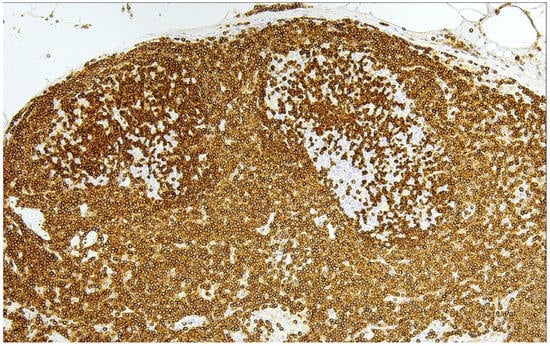

10. Primary Cutaneous Follicle Center Lymphoma